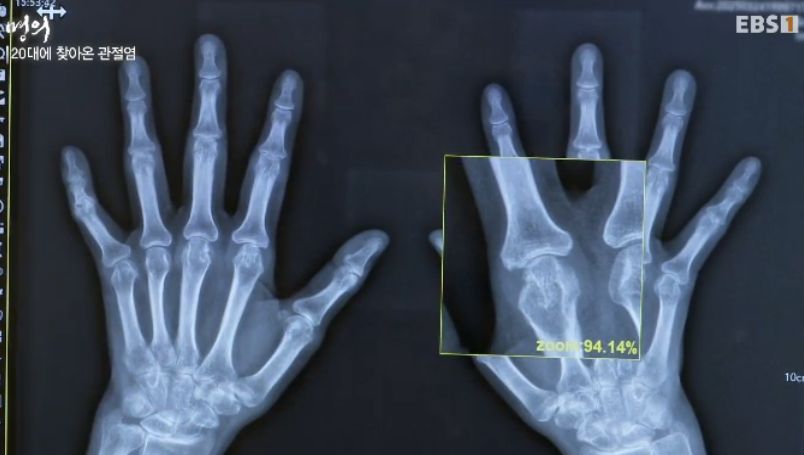

20대에 찾아본 관절염

"류마티스는 염증이 연골을 녹이기 때문에

땅에 가라앉듯이 두 개가 붙어버려요"

29살에 관절변형된 사례)

진단은 피검사와 엑스레이. 필요하면 관절초음파 등.